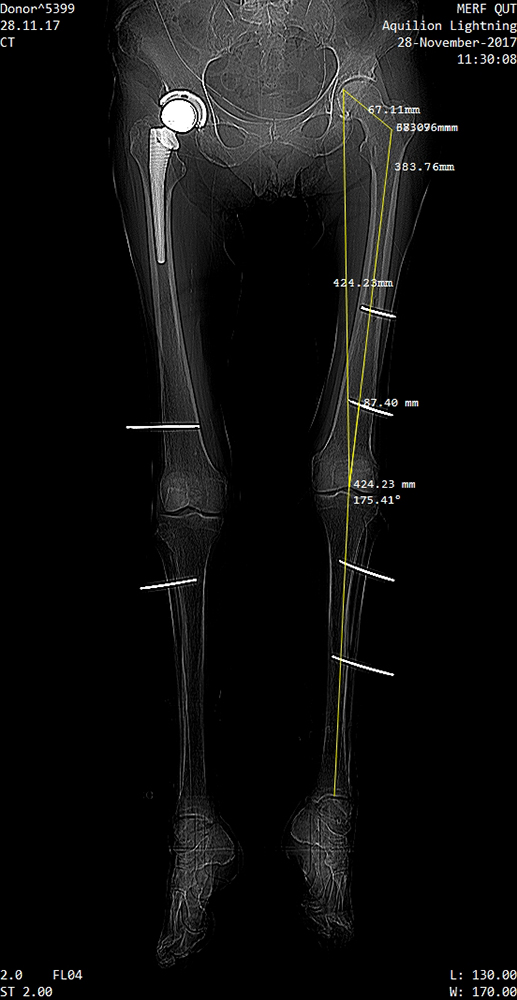

A leg manipulator robot (Figure 2b) was developed (patent No. 2019900476) with a foot interface (Figure 3b) to the leg. Ethical approvals were gained for three Cadaver experiments as detailed in Table I. Firstly the robustness and accuracy of existing rigid bodies from OptiTrack were tested. A ten camera system were installed on a 3mx3mx2.5m structure (Figure 2a), and calibrated with an accuracy wand. The second experiment tested the designed RBs and CT scan measurements as shown in Figure 8. For the final experiment a refined process, CT scans and RBs designs were used.

Refer to caption

(a) Femur Anatomical and mechanical axes

(b) Mounted RBs and markers.

Figure 8: CT Scan of a cadaver leg.

The femur mechanical axis is defined as the link from the hip joint centre to the centre of the condyles on the knee as shown in Figure 7 and 8(a). The femur vector that describes the hip rotations relative to the world frame is:

Key parameters for robotic leg manipulation include the rotations and translations of each joint, which is calculated from the combination of CT, optical tracking and the mathematical model. It forms an integrated system during surgery for real-time anatomical measurements. Angles for each joint were calculated from the cadaver data and are shown in Figure 9a to 9d. Figure 9e and 9f show snapshots from video analysis at time 5 and 45 seconds, which is marked with black vertical lines on each of the angle graphs. For clarity, only the first 60 seconds are shown. The accuracy of the vector’s positional data (0.3mm), ensures that the calculated angles are accurate.